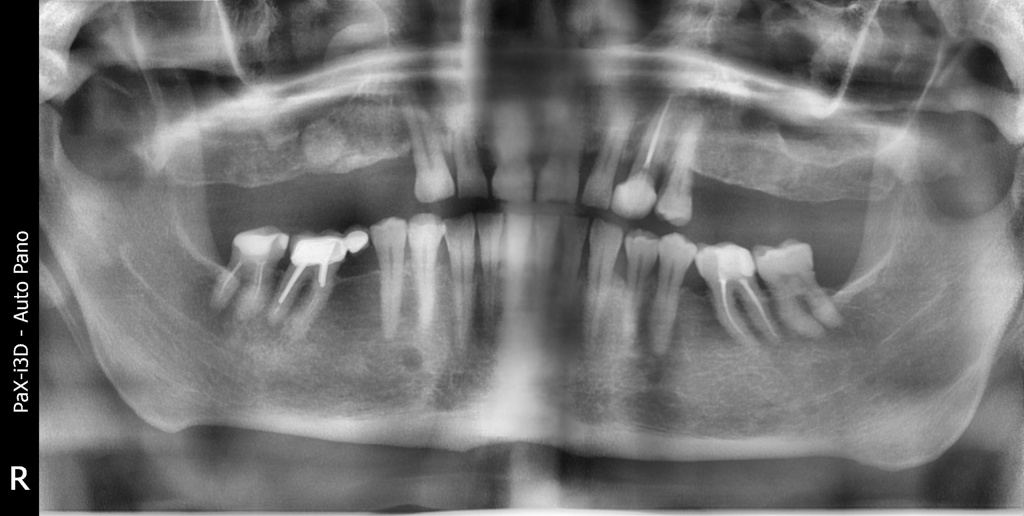

Плановая имплантация в жевательном отделе перед тотальной реабилитацией с поднятием прикуса.

Осложнения: сахарный диабет

По результатам диагностики принято решение установить имплантаты AnyRidge и AnyOne с использованием хирургических шаблонов Bonepen 3D.